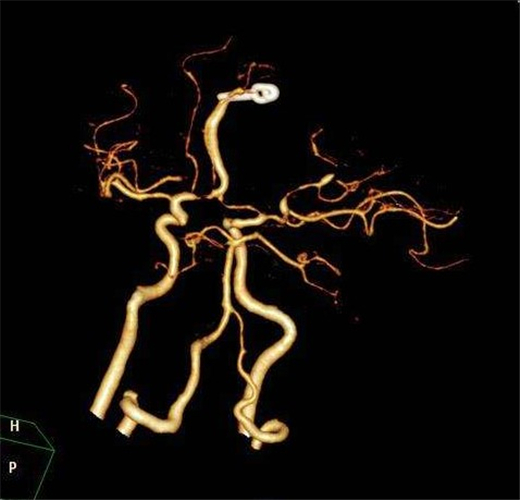

腦血管痙攣造影

腦血管痙攣